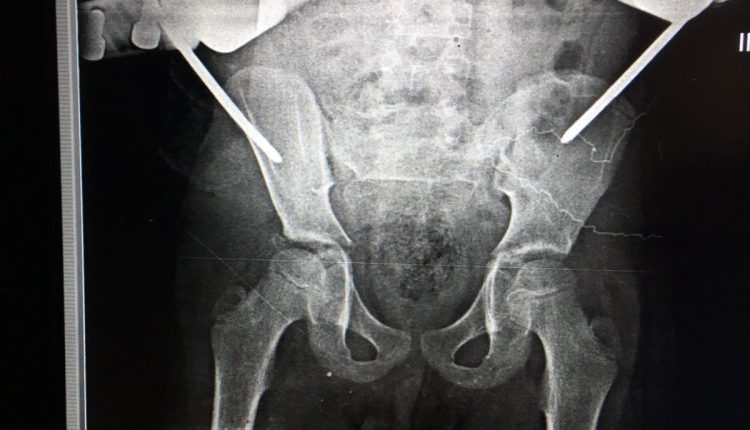

قام الفريق الطبي بقسم جراحة العظام بمستشفي الزقازيق العام، بقيادة الدكتور محمد راشد رئيس القسم، والدكتور أحمد عبدالسلام استشاري جراحة العظام، والدكتور أحمد نوفل مقيم جراحة العظام، تحت إشراف الدكتور جلال بليغ مدير المستشفى، بإجراء جراحة متقدمة ذات طابع خاص، لتثبيت كسر خلعي بمفصل الحوض باستخدام مثبت خارجي، لطفل يبلغ من العمر ٩ سنوات، وذلك بعد إجراء كافة الفحوصات الطبية والأشعات اللازمة، والمريض الآن بحالة جيدة ومستقره، ويتلقي العلاج اللازم بقسم جراحة العظام تحت متابعة الأطباء بالمستشفي.